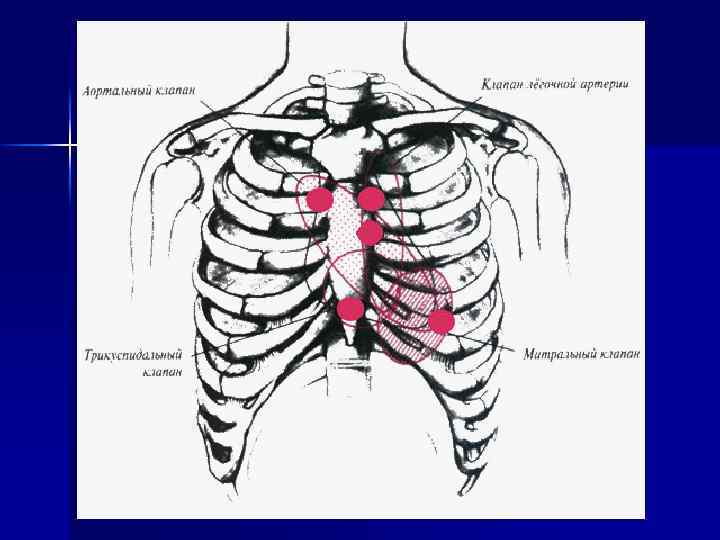

Точки выслушивания шумов Общие закономерности: 1) лучше всего шумы выслушиваются в точках аускультации тех клапанов, в области которых они образовались 2) шумы хорошо проводятся по направлению тока крови 3) шумы лучше выслушиваются в той области, где сердце прилежит к грудной клетке и не прикрыто легкими n